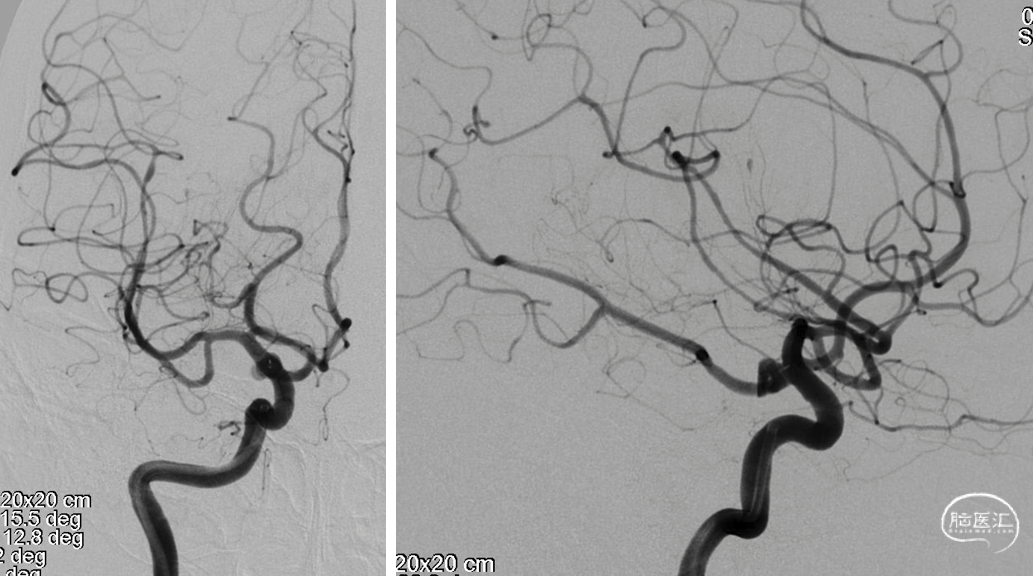

DSA

左侧多发动脉瘤

右侧:平均宽度(5.5+3.9)=4.7mm,最小深度2.8mm,选择SL5x2

VIA微导管到位\WEB释放

WEB释放后造影

术后造影

术后CT